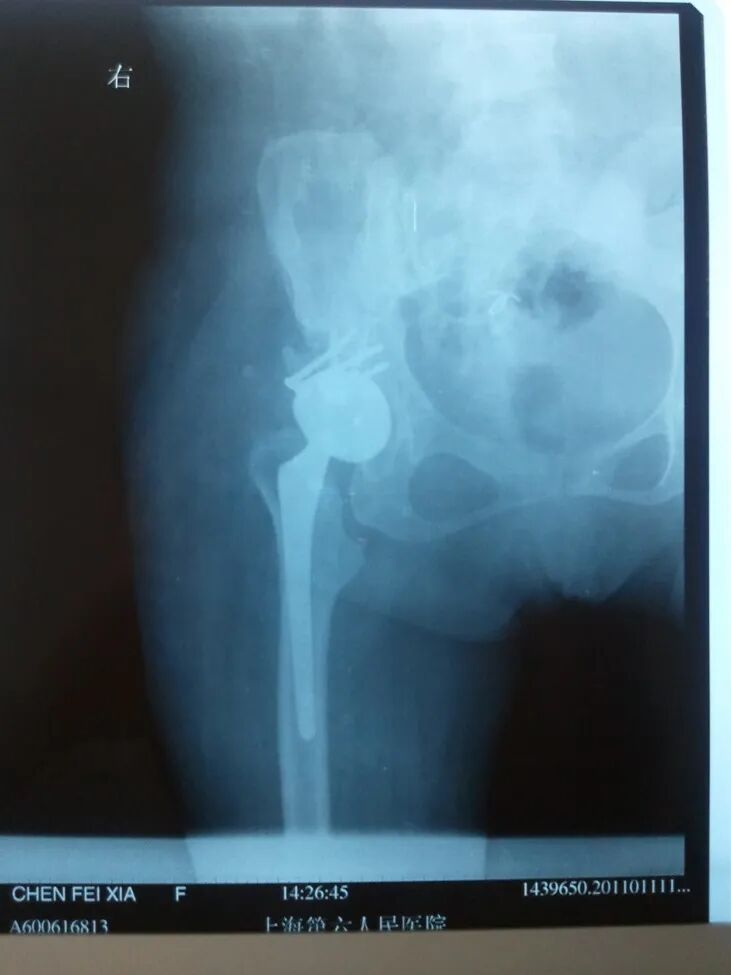

先看病例!

女性患者,48岁,右髋疼痛25年,加重1年

术后5天,脱位

切开复位

术后4月,再一次脱位

屋漏偏遭连夜雨